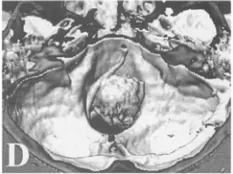

三维增强CT示肿瘤以宽基底附着于枕骨大孔前缘中线两侧,占据大孔腔隙超过2/3;右侧椎动脉被肿瘤包绕(D)。由于椎动脉系统是供应大脑血液的两套主要系统之一,若椎动脉在手术中受损,可能会导致严重的并发症,从而影响患者的预后和术后的生活质量。